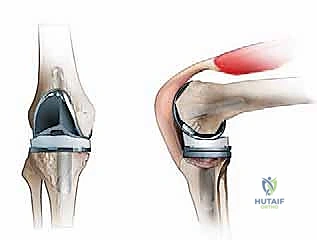

A profound understanding of proximal tibial anatomy and the biomechanics of load transfer is mandatory for managing challenging tibial defects. The proximal tibia expands from a dense cortical diaphyseal tube into a broad metaphyseal flare, composed primarily of a thin cortical shell surrounding a vast network of cancellous trabecular bone. During primary total knee arthroplasty, the tibial component is designed to rest on the dense subchondral bone of the proximal metaphysis.

In the revision setting, this critical metaphyseal bone is frequently absent or structurally compromised. The most common areas of deficiency involve the posterolateral and medial tibial plateaus. The medial tibial plateau normally bears approximately sixty percent of the axial load during the stance phase of gait. Consequently, uncontained defects in the medial plateau are particularly detrimental to the biomechanical stability of a revision construct.

When metaphyseal bone loss is substantial, the biomechanical paradigm of implant fixation must shift from metaphyseal support to diaphyseal bypass. This is conceptualized through the principle of zonal fixation. Zone 1 represents the articular surface and epiphysis, Zone 2 encompasses the metaphysis, and Zone 3 is the diaphysis. When Zones 1 and 2 are compromised by massive osteolysis or structural defects, stable fixation can only be achieved by engaging the dense cortical bone of Zone 3.

Bone grafting serves to reconstitute the bone stock in Zones 1 and 2. While diaphyseal stems provide immediate mechanical stability and bypass the defect, the long term success of the reconstruction often relies on the incorporation and remodeling of the bone graft to restore physiological load transfer to the proximal tibia. Impaction bone grafting utilizes tightly packed cancellous allograft to convert shear forces into compressive forces, providing a stable bed for cemented components. Structural allografts, conversely, are utilized to replace massive uncontained segmental defects, restoring the anatomical joint line and providing immediate structural support, albeit with a slower rate of biological incorporation.